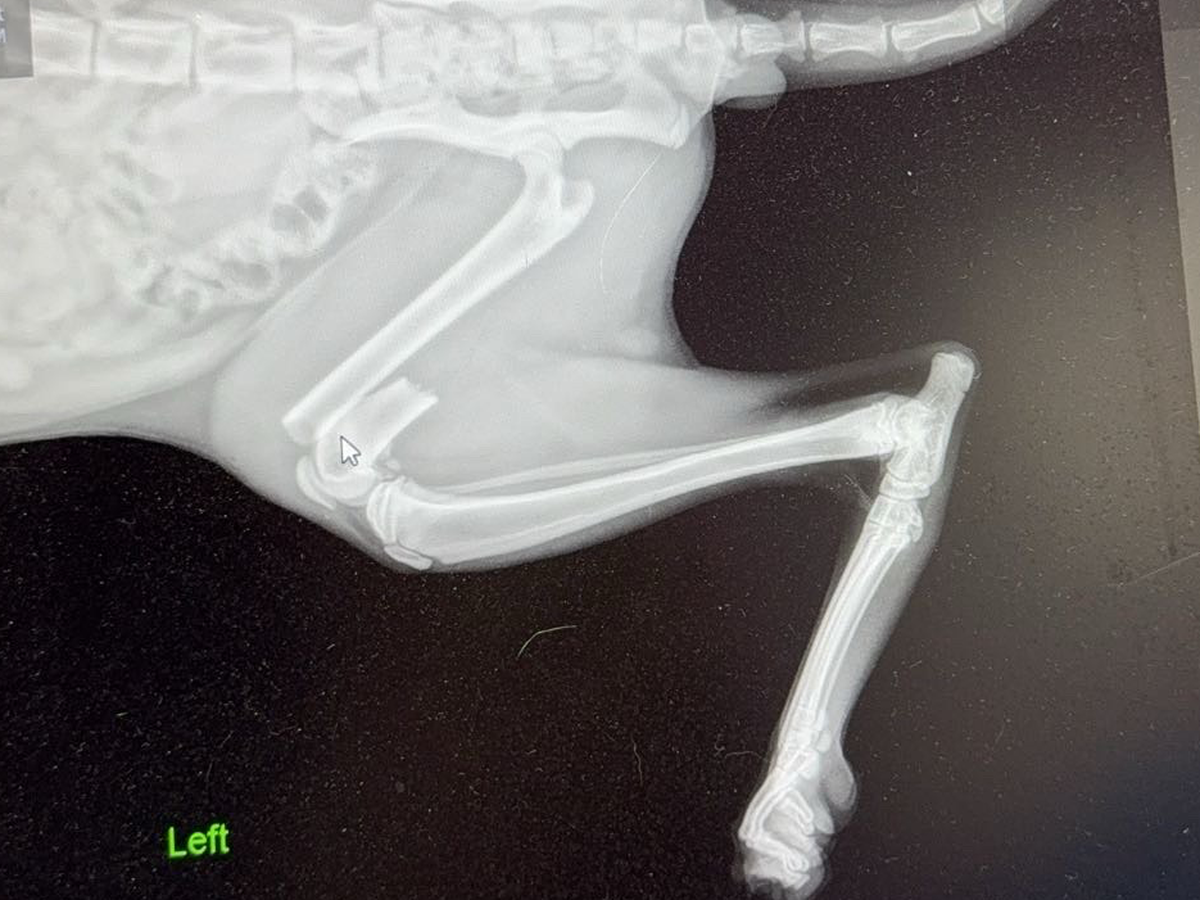

We are raising money for this sweet boy to get his leg fixed. He is only a year-old tuxedo male cat and we found him on the side of the road in a box with his sister. They seem bonded, so we brought them to the vet together to discover he broke his leg. It happened when he was on a dresser, and he jumped up to grab onto something and he missed, fell back down, and landed wrong on his left back leg. Options are orthopedic surgery or amputation. We would like to save his leg the best we can, so anything will help. We have only had this bonded pair of cats for a day, and we’re trying to give them a good life. I would hate to not be able to get surgery for it. Right now we are raking up to $800 and that’s just for antibiotics, a splint, sedation, just to hold him up until he gets surgery. Anything will help. Thank you so much.